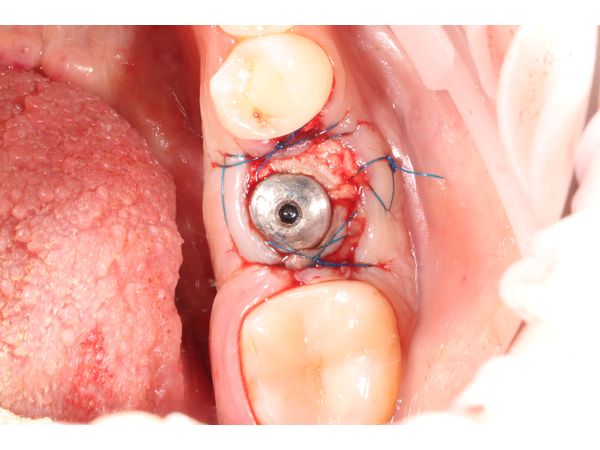

- установили дентальный имплант размером 4,3×10 мм фирмы SNUCONE в межкорневую перегородку;

- заполнили лунки корней биотропным ксенографтом (остеопластическим материалом).

Через 2 недели женщине сняли швы. Слизистая была бледно-розового цвета, без признаков воспаления. Гигиена полости рта удовлетворительная, динамика заживления положительная.